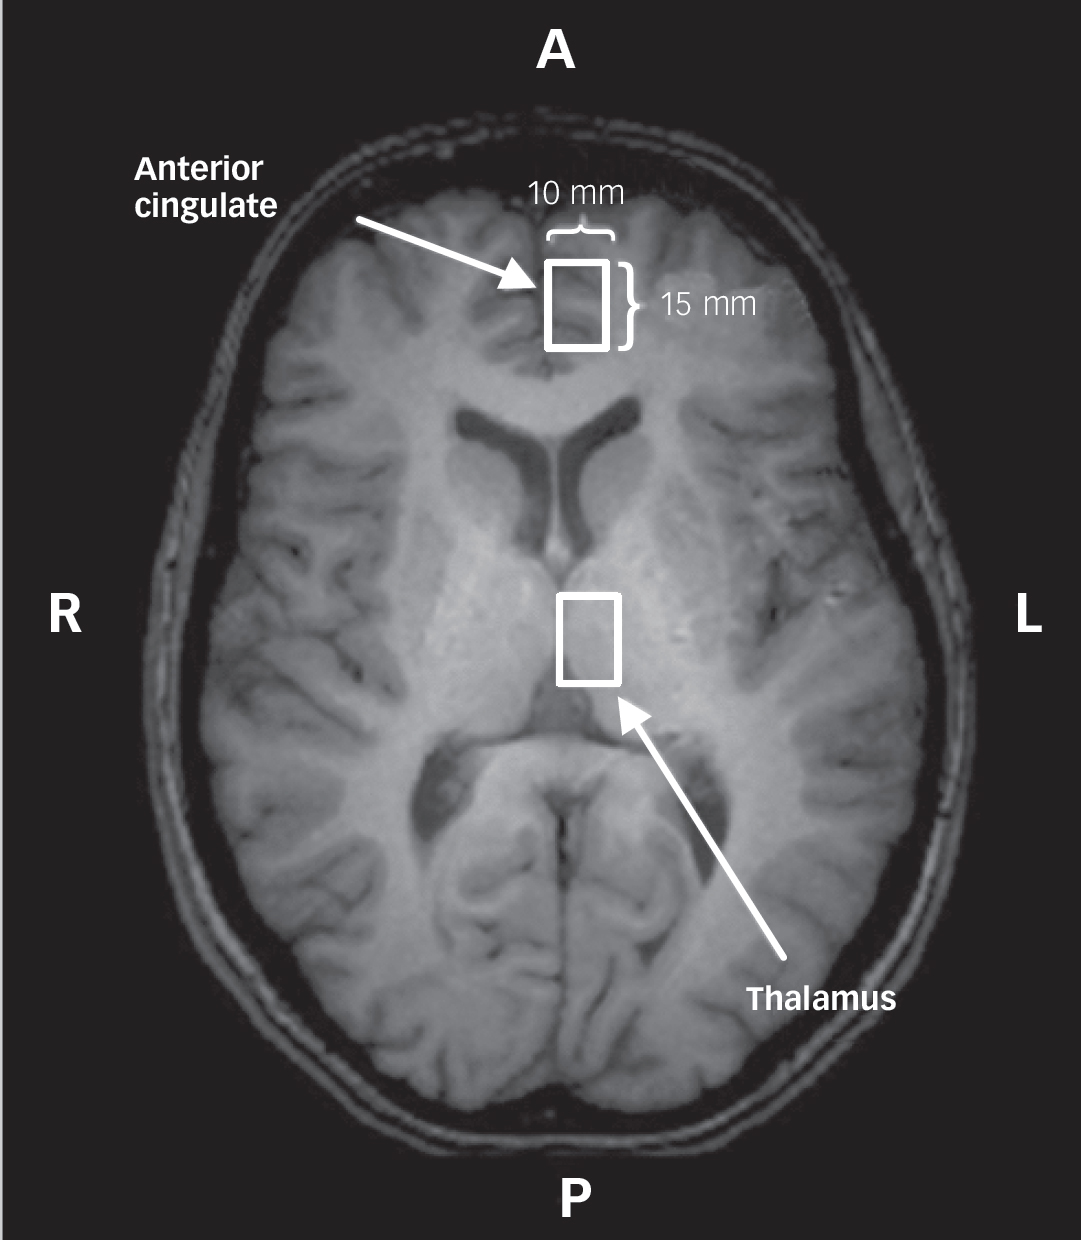

Data were acquired with a 4.0 T whole body magnetic resonance scanner located at the Centre for Functional and Metabolic Mapping of the Robarts Research Institute, London, Ontario, Canada. A circularly polarised transmit/receive head coil was used. The magnetic resonance system was monitored by a technician, who performed weekly quality control using the same phantom and with the echo planner imaging sequence. All data acquisition and quantification procedures were performed as described in our previous study: Reference Théberge, Williamson, Aoyama, Drost, Manchanda and Malla8 imaging, voxel positioning (left anterior cingulate and left thalamus;Fig. 1), voxel size (1.5 cm3), shimming, spectroscopy (STEAM sequence, echo time (TE) 20 ms, mixing time 30 ms, repetition time (TR) 2000 ms, dwell time 500 μs), pre-processing, exclusion criteria of magnetic resonance spectrum, spectral fitting and metabolite quantification. Only metabolites with a group coefficient of variation ((group standard deviation/group mean)×100%) less than 75% are reported: NAA, glutamate, glutamine, choline, total creatine (tCr), myo-inositol in the anterior cingulate and the thalamus; taurine and scyllo-inositol in the thalamus only. The ‘total glutamatergic metabolites’ (tGL) refers to a sum of glutamate and glutamine levels quantified individually. Complete description of the magnetic resonance imaging (MRI) and MRS methods can be found in the online data supplement.

Fig. 1 A white-coloured rectangle represents a spectroscopy voxel in the left anterior cingulate and the left thalamus.

Localisation was performed using a transverse T 1-weighted image, in which the landmark of each region is seen. A, anterior; L, left; P, posterior; R, right.